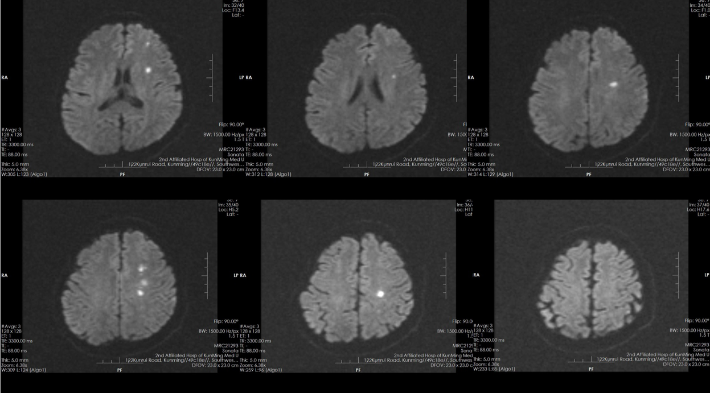

CTP

4. 脑侧支循环:术前应用结构影像学和功能影像学方法充分评估脑侧支循环,筛选血流动力学障碍引起缺血症状发作的患者,可能最适合血管内治疗。

--CTP有低灌表现

--DSA显示左侧颈内虹吸段狭窄约72%。前交通开放,右侧大脑前动脉通过前交通动脉向左侧大脑前动脉、大脑中动脉供血区有代偿供血。

--双抗治疗下仍有缺血症状发作。评估有手术指征,无手术禁忌。